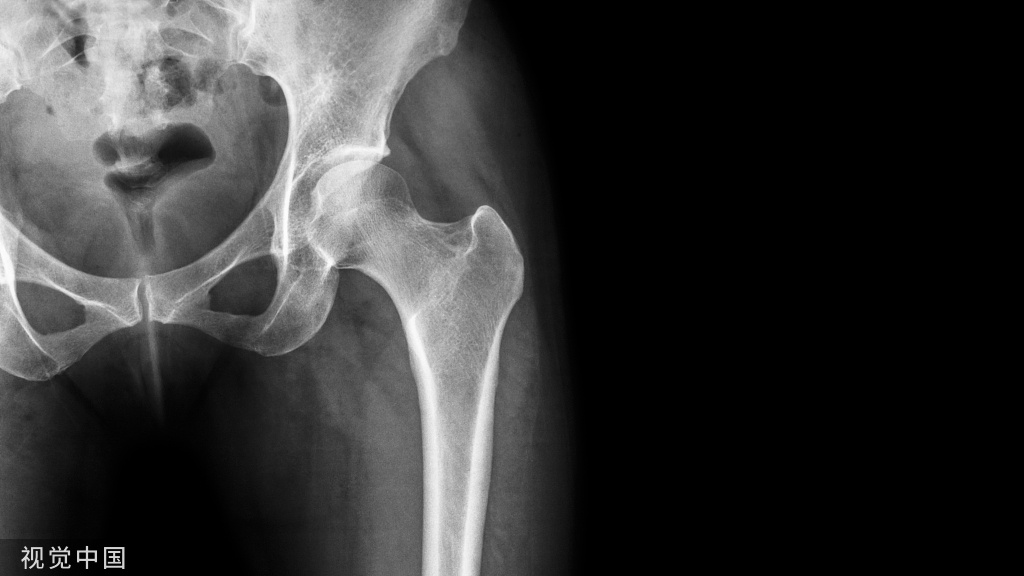

• 一方面,由于增龄造成骨重建失衡,骨吸收/骨形成比值升高,导致进行性骨丢失;

• 另一方面,增龄和雌激素缺乏使免疫系统持续低度活化,处于促炎症状态。

①炎症介质,如肿瘤坏死因子α(tumor necrosis factor-α,TNF-α)、白介素(interleukin,IL)-1、IL-6、IL-7、IL-17 及前列腺素 E2(prostaglandin E2,PGE2)均能诱导 M-CSF 和RANKL 的表达,刺激破骨细胞,造成骨量减少。②雌激素和雄激素在体内具有对抗氧化应激的作用,老年男性性激素结合球蛋白持续增加,使睾酮和雌二醇的生物利用度下降,体内的活性氧类堆积,促使间充质干细胞、成骨细胞和骨细胞凋亡,使骨形成减少。③年龄相关的肾上腺源性雄激素生成减少、生长激素(growth hormone,GH)- 胰岛素样生长因子(insulin-like growth factor,IGF)轴功能下降、肌少症和体力活动减少造成骨骼负荷减少,也会使骨吸收增加。④随增龄和生活方式相关疾病引起的氧化应激及糖基化增加,使骨基质中的胶原分子发生非酶促交联,导致骨强度降低。